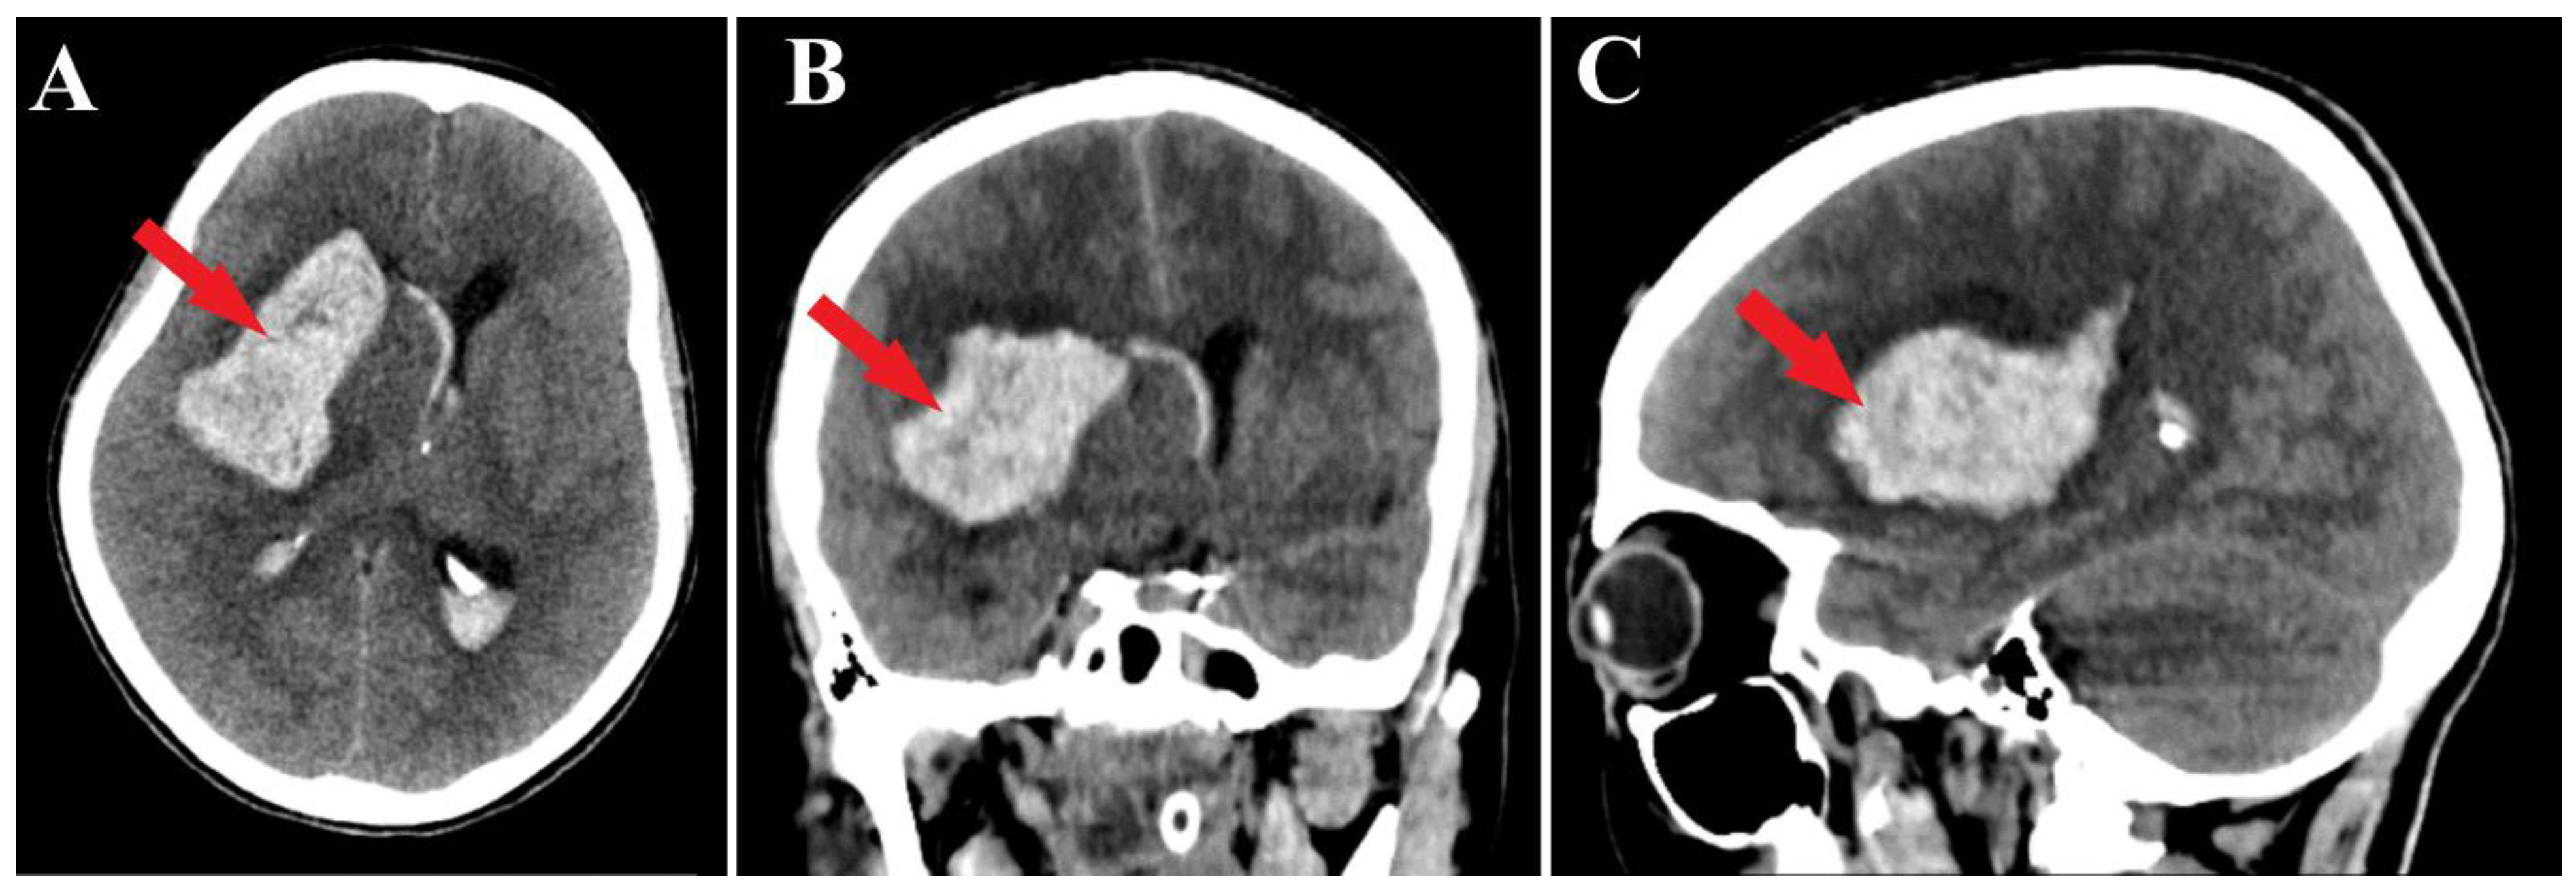

A 44-year-old patient was admitted to our clinic for sudden left hemiparesis MRC 1/5 occurring in the apparent health status 48 h prior to admission, followed by the deterioration of consciousness that become gradually worse, with the patient becoming comatose. She was admitted to our clinic with GCS = 7 points (eye response—2 points, verbal response—2 points, motor response—3 points), orotracheally intubated, and mechanically ventilated. Neurological examination on admission revealed a left hemiparesis, predominantly in the brachial region and comatose state. A brain non-contrast CT scan revealed a voluminous right fronto-temporal intraparenchymal hematoma with panventricular infiltration, significant mass effect on the right lateral ventricle, and 1.5 cm displacement of the midline. Otherwise, normal cerebroventricular CT appearance was seen (Figure 1). Angiography was performed through the selective injection of the internal carotid artery bilaterally, right external carotid artery, and left vertebral artery. Right temporal arteriovenous malformation with arterial afferents from the right anterior choroidal artery and right-sided middle cerebral artery was observed, Spetzler Martin grade III (Figure 2). A nidus of approximately 2/1 cm in size with several intranidal aneurysms was also observed (Figure 3). A single vein was draining into the right cavernous sinus, through an intermediate venous source.

Figure 1.

Preoperative CT scan. Axial section (A) highlights the intraparenchymal hematoma (red arrow); moreover, frontal (B) and sagittal (C) sections depict the massive hematoma with panventricular implication too (red arrows).